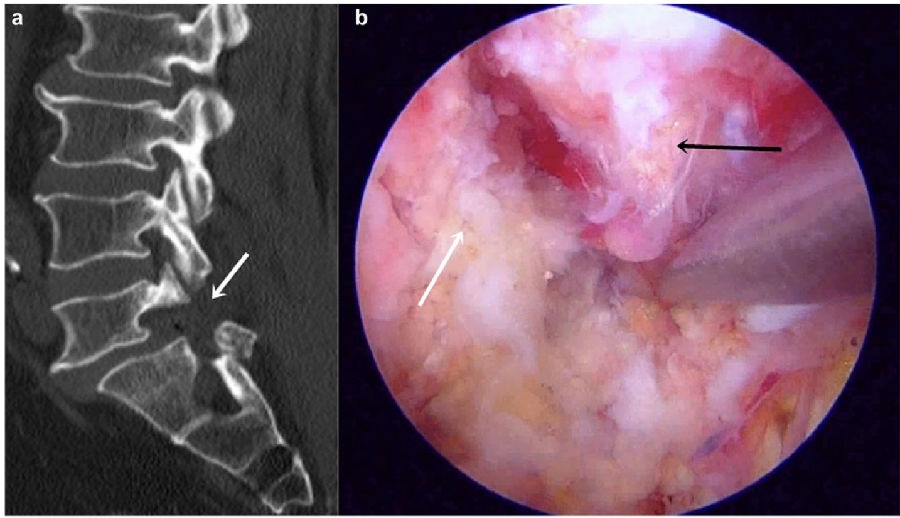

八、医源性不稳定(0.88%)

发生率0.6%,明显低于开放式手术,小关节突关节损伤是主要原因。上腰椎(L1~L3)病变、存在狭窄椎板和脊柱矢状面失衡的患者减压过程几率更高。

病例(关节突损伤)

男,52岁。

主诉:腰痛20余年,双下肢疼痛10余年,加重4天。

查体:双侧直腿抬高试验及加强试验(-),双侧膝腱反射及跟腱反射未引出,Babinski征(-)。

思考及建议

使用磨钻从棘突基底部与上椎板下缘交界处切开

术前CT测量关节突切除范围

L3-4及以上节段,对侧入路切除椎间盘